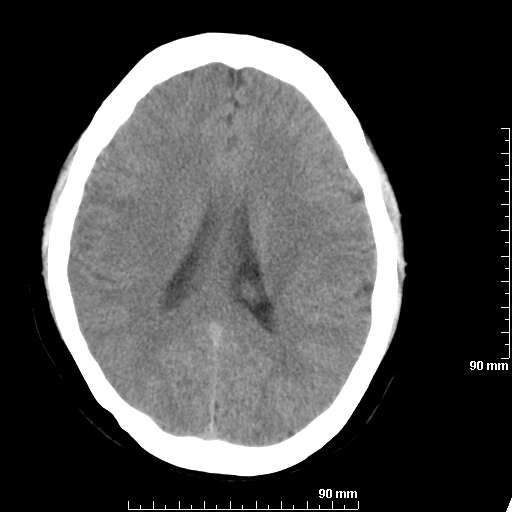

[维修案例解析] 大家猜猜看,这个伪影是怎样产生的.

二马日王 显示全部楼层 发表于 2011-6-9 18:12:55 |阅读模式

我院西门子单排CT由于一零件受损而产生的伪影.

哈哈,都不是。是虑线器fiter裂损。大家没想到吧。

哦,跟脑出血有点像哦

形状不规则,边缘模糊。比较特殊的一种伪影哈!

这种伪影很常见!伪影应该是在视野的中心的。

西门子的虑线器fiter裂损这才是很难见的问题,GE的最常见

虑线器老化,中间崩裂一块掉了

确实是虑线器,但是很少见

确实是虑线器,听说过,赞一个